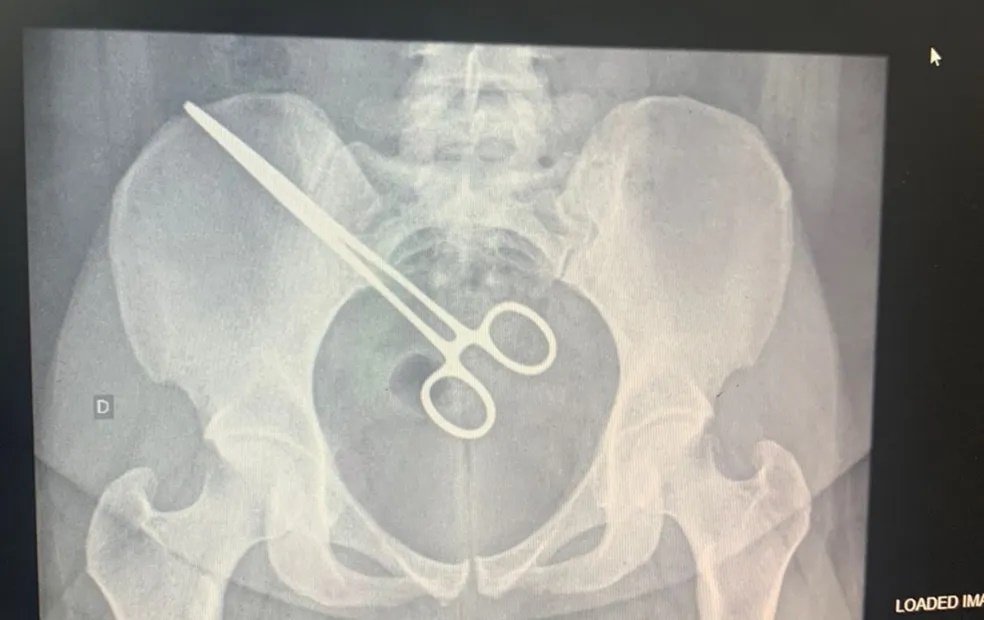

Instrumento foi descoberto ao passar em detector de metais do presídio. Pinça estava no corpo há dois meses, após cirurgia para retirada de feto na Santa Casa de Araçatuba (SP). Hospital informou que investiga o caso.

Após o episódio no CDP, a paciente foi até a Santa Casa, onde fizeram um exame de raio X e constataram que a pinça estava dentro dela. A mulher foi internada novamente no hospital, na segunda-feira, para cirurgia de retirada do instrumento.